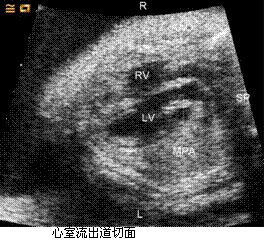

孕妇,36岁,孕2产1孕25周,无特殊病史,实验室检查无明显异常,心脏超声所见如下图。 GJ33_22_29.gifGJ33_22_29_1.gif (L-左侧,R-右侧,LA-左心房,RA-右心房,LV-左心室,RV-右心室,AAO-升主动脉,MPA-主肺动脉,SP-脊柱)